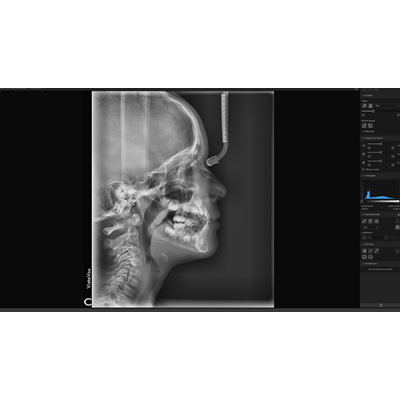

Creating treatment plans and monitoring treatment progress

With VistaSoft Trace, images can be easily overlaid from various stages of the treatment so that progress can be monitored. The software also supports the simulation and display of treatments based on planning data, so that the potential success of a course of treatment can be illustrated even before work gets under way.